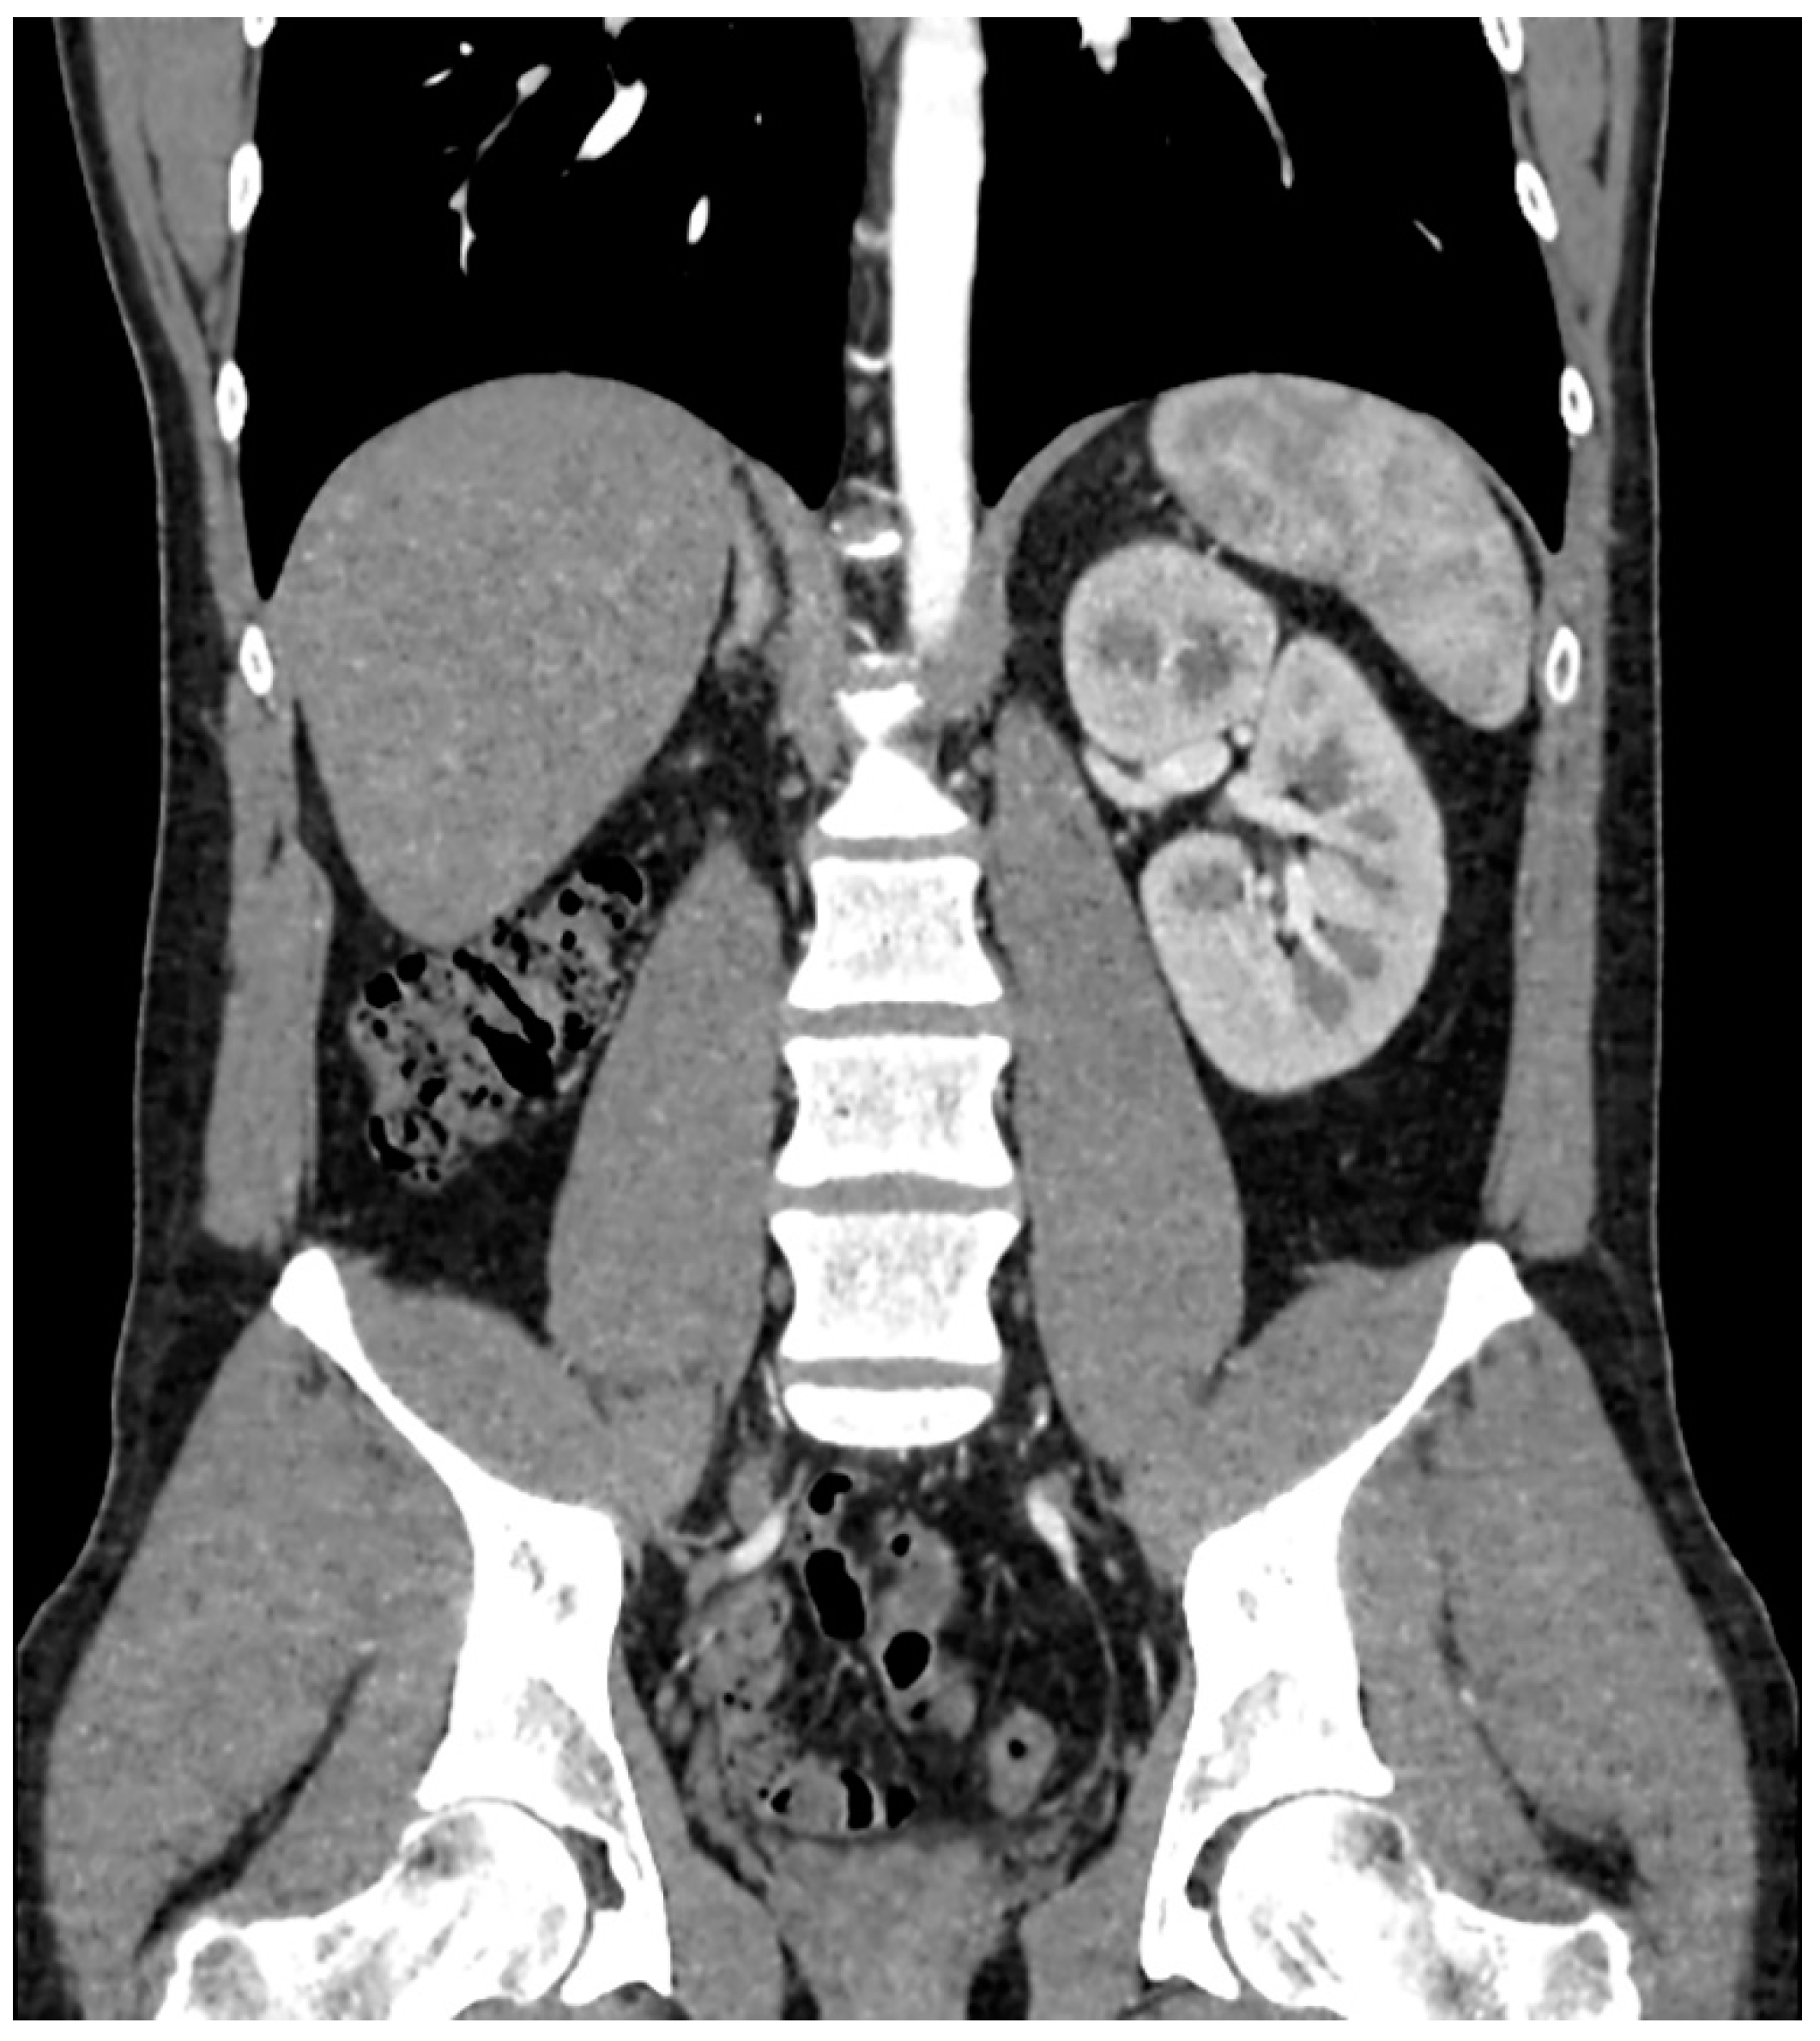

Zinner Syndrome—A Rare Cause of Recurrent Epididymitis and Infertility

2. Case Report